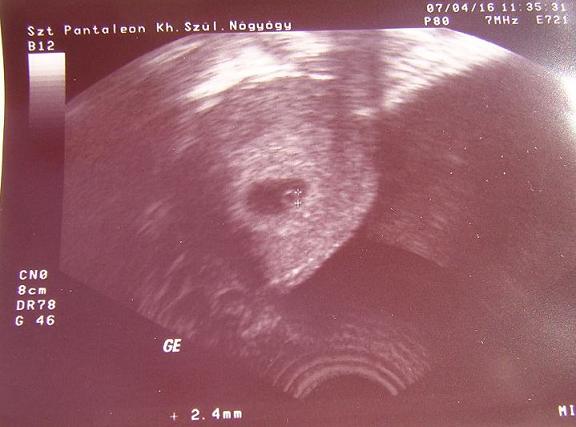

Elmondtam neki mindent, egyből azt mondta, hogy hú de korán van még, és persze az uh-n sem látszott semmi!

Bár azt mondta, tapintani már lehet (és mivel nagyon fájt a hasam, jó, hogy eljöttem, legalább, hogy lássuk, nincs-e baj), és berendelt jövő hétre a kórházi uh-ra - remélem akkor már látok dobogni vmi kis szivecske-félét!!! A hosszú ciklusom (30-34 napos) alapján a fogamzás ápr. 4-e körül lehetett, így most 4 hetes terhes vagyok.